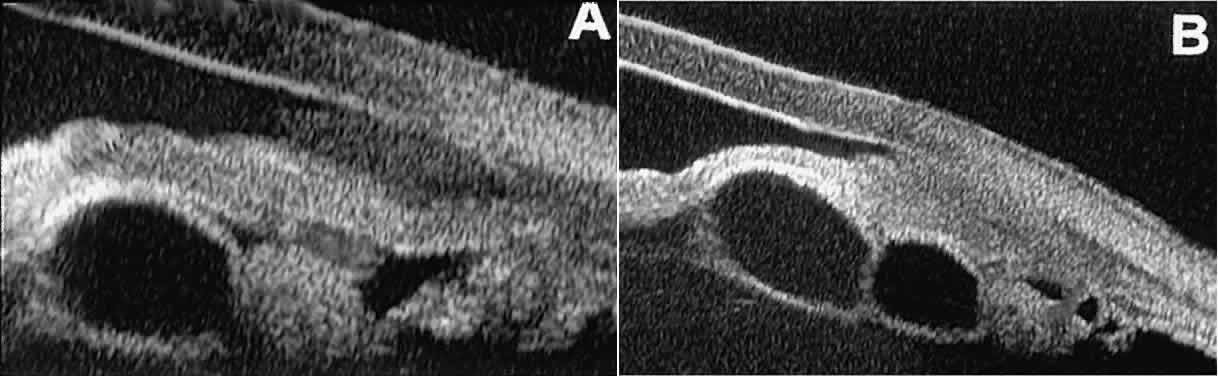

Stratified squamous epithelial cysts (Fig. 23) are almost exclusively unilateral and unifocal,15 have substantially thicker walls than do primary neuroepithelial cysts, and usually contain prominent intracavitary particles (desquamated epithelial cells). Almost all such cysts involve the peripheral iris and angle region. Such cysts are usually secondary to prior ocular surgery or laceration in which conjunctival epithelial cells were implanted into the iris stroma.

Fig. 23. UBM features of stratified squamous epithelial cysts of iris. A. Thick-walled implantation cyst of stratified squamous epithelium replacing normal iris. Note intracavitary particles. B. Bilobed stratified squamous epithelial inclusion cyst of iris with prominent intracavitary particles.

Secondary neuroepithelial cysts occur rather frequently in association with solid tumors of the iris or ciliary body.15 On UBM (Fig. 24), such cysts appear quite similar to the primary neuroepithelial cysts described above; however, they are associated with a solid mass arising within the iris or ciliary body.

Fig. 24. UBM appearance of neuroepithelial cysts associated with solid tumors of the iris and ciliary body. A. Single neuroepithelial cyst associated with iris melanoma. B. Multiple neuroepithelial cysts associated with iridociliary melanoma.